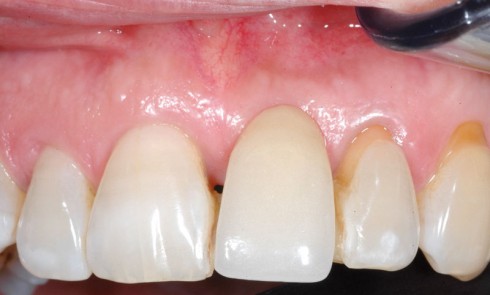

Article réservé à nos abonnés Parodontie et prothèse

Les relations qui unissent prothèse et parodonte sont souvent conflictuelles et complexes. Afin d’éviter ces conflits entre impératifs prothétiques et...